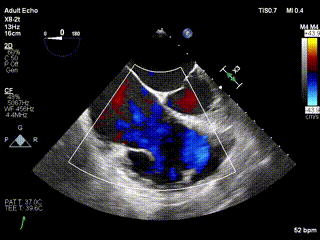

2021年12月24日,復(fù)旦大學(xué)附屬中山醫(yī)院葛均波院士團(tuán)隊成功應(yīng)用LuX-Valve Plus為一例極重度三尖瓣反流(TR)合并房顫、房缺的患者完成了經(jīng)血管三尖瓣置換術(shù),這是在前基礎(chǔ)上,本周完成的第三例經(jīng)血管三尖瓣置換手術(shù),葛均波院士、周達(dá)新教授等與心外科魏來教授、賴顥教授,心超室的潘翠珍教授、李偉教授及麻醉科的郭克芳教授共同完成了本周手術(shù),均獲得圓滿成功!患者術(shù)后超聲顯示無TR,臨床癥狀明顯改善。本周手術(shù)的成功也為LuX-Valve Plus救治性臨床研究添上了濃墨重彩的一筆。

三例患者入院后,葛均波院士團(tuán)隊周達(dá)新教授、潘文志教授、張源博士、陳莎莎博士及心超室的潘翠珍教授、李偉教授對患者的情況進(jìn)行詳細(xì)評估和討論,最終決定為三例患者選擇LuX-Valve Plus40mm、50mm和50mm型號的瓣膜進(jìn)行手術(shù)治療。手術(shù)后即刻拔除氣管插管,術(shù)后患者三尖瓣反流癥狀得到顯著改善,復(fù)查心超結(jié)果顯示人工三尖瓣瓣膜支架固定穩(wěn)定,瓣葉關(guān)閉形態(tài)未見異常,未見明顯反流。